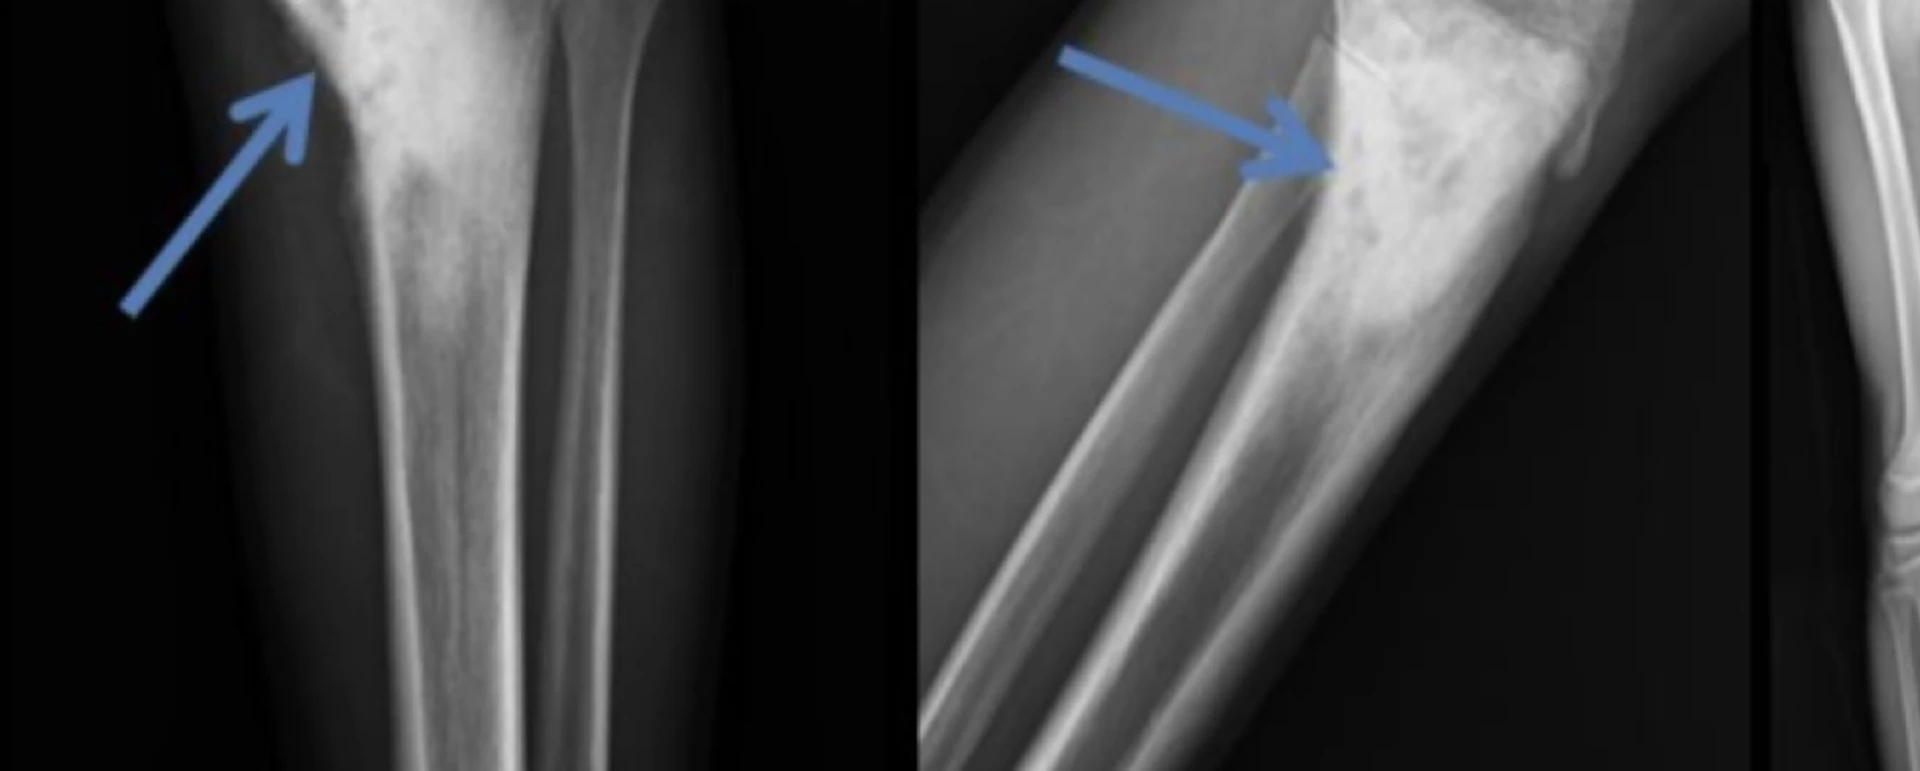

OSTEOSARKOM

Osteosarkom, mikroskop altında incelendiğinde immatür (olgunlaşmamış) kemik üretimi ile karakterize edilen kötü huylu (malign) bir kemik tümörüdür. Genellikle kemikten kaynaklanır ancak nadiren kas veya bağ dokusu gibi yumuşak dokulardan da gelişebilir.

Osteosarkom vakalarının %70–80’i uzun kemiklerde, özellikle de metafiz bölgesinde (ekleme yakın uç kısımlar) görülür.

En sık yerleşim bölgeleri:

1. Distal femur (uyluk kemiğinin alt kısmı)

2. Proksimal tibia (kaval kemiğinin üst kısmı)